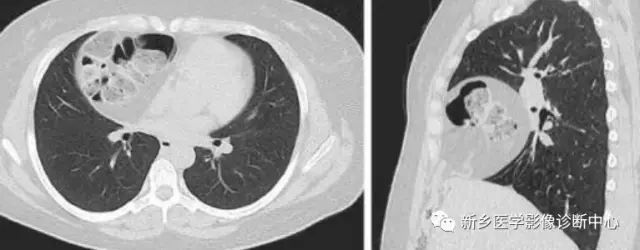

CT:贲门级部分胃体组织通过食管裂孔进入胸腔内,位于膈上,其上段食管明显扩张。

CT:食管裂孔疝以食管下端纵隔内有疝囊检出为直接征象。疝囊以假肿块样改变为特征,可有软组织密度肿块,也可表现为囊性液体密度影,部分疝囊以食管下端扩张改变为影像表现,经食管裂孔向膈下胃腔延续为主要特点。疝囊外壁光整,内壁可呈锯齿状,可见胃黏膜影像。胃壁充盈好则厚度较薄,疝囊带状管腔扩张样改变,内有潴留食物;充盈不佳者囊壁较厚,表现为软组织团块样影,内有少量液体或气体影。采用CT增强扫描,胃壁与疝囊囊壁均匀一致。

如发现疝囊壁不规则增厚,外壁不光整,周围淋巴结肿大等征象,高度怀疑食管裂孔疝合并肿瘤。需进一步胃镜活检检查。食道静脉曲张CT平扫表现为食管下端管腔轻度扩张、管壁增厚,黏膜增厚类似胃黏膜,易误诊,食道静脉曲张是肝硬化、门静脉高压的重要并发症,常与胃底静脉曲张并存;CT增强扫描显示食道下段、胃底部扩张血管影,同时有肝硬化表现,结合临床病史鉴别不难。食管下端憩室表现为囊袋状突出食管腔外的局部管腔扩张,内有气液平面,但胃腔与食管壁间无延续的胃黏膜像,且憩室下方正常食管段明显变窄,隔下有呈扩大改变的胃腔。